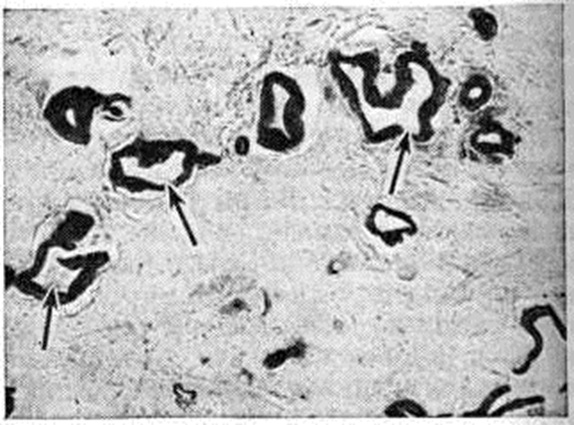

Хронический очаговые Гепатит (например., при бруцеллёзе, саркоидозе, туберкулёзе, альвеококкозе) имеют специфическую патологический картину, свойственную общей патоморфологии этих заболеваний (рисунок 1—4).

При поражении печени некоторыми грибками (актиномикоз), простейшими (амебиаз, балантидиаз) и гельминтами (аскаридоз, клонорхоз, фасциолез) наблюдаются гнойные Гепатит с множественными абсцессами. И. В. Давыдовский подчёркивал, что гранулематозный процесс более стереотипен, чем специфичен, так как обусловлен иммуногенезом и однообразием образующих гранулему клеточных элементов, которые при различных нозологических формах отличаются лишь своими сочетаниями.

Рис. 4. | ||